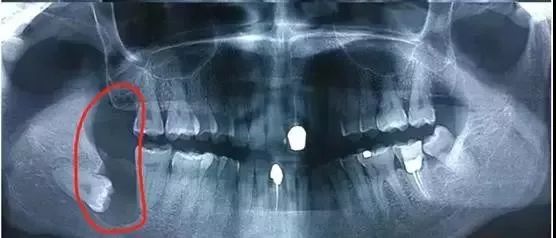

智齿在X线片上很清晰▼

阻生齿主要有以下几类▼

令人“不省心”的阻生齿▼